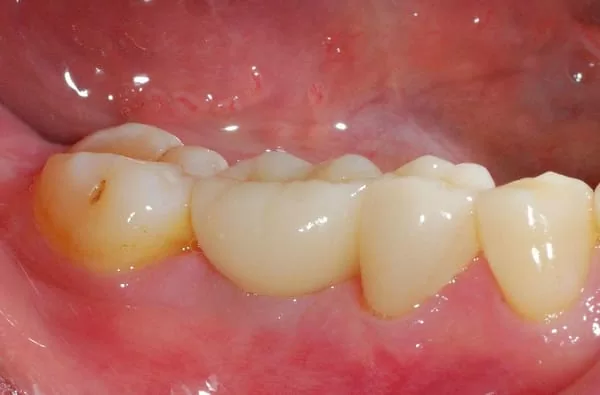

經牙嵴保存術後再植牙,醫師說:這就是"植牙癒合帽"周圍牙嵴豐隆度很好~ (# ̄▽ ̄#)

細心的醫師先在石膏模型上模擬製作植牙全瓷冠給我看~